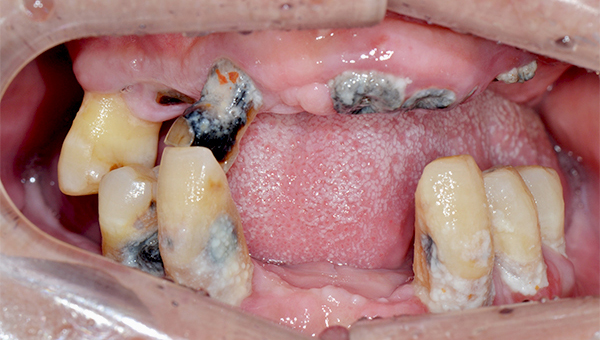

2025.02.07

치료 전